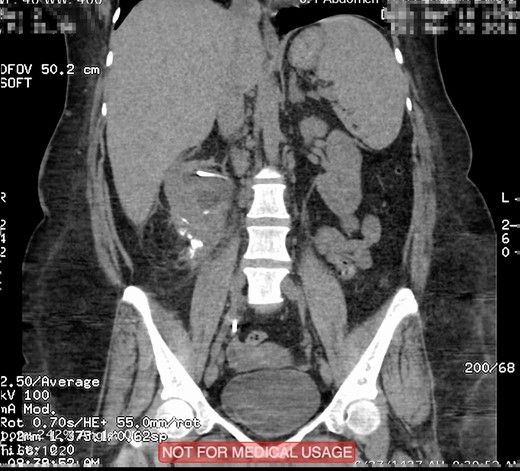

This is a 45-year-old female patient known to have diabetes mellitus and old cerebrovascular attack presented with right flank pain. Laboratory investigations revealed normal WBC count with a hemoglobin 10.4 mg/l. Radiological investigation showed right a 20 mm right renal stone (Fig. 1). Patient underwent FURS-L using a 10/12Fr Ureteral Access sheath. We did endoscopic renal exploration plus laser lithotripsy using Flex-Xc STORZ. The irrigation was under hydrostatic pressure of 80 cm H2O. The procedure was uneventful with an operative duration of 88 minutes. However, severe extravasation was noted at the end (Fig. 2). Six hours postoperatively the patient started to have high grade fever with a sudden drop of hemoglobin level to 6.6 mg/l. Immediate abdominopelvic CT scan with contrast was carried out showing severe right subcapsular renal hematoma. This complication was managed conservatively through proper antibiotics, blood transfusion and good hydration for 7 days. The patient was seen in the outpatient clinic 2 months later with a new abdominopelvic CT scan which showed a regression of subcapsular renal hematoma and surprisingly migration of stone fragments into the regressed subcapsular hematoma (Fig. 3). On the other hand, the upper urinary tract was free of stones.

Plain abdominopelvic CT, coronal view showed migrated stone fragments into the regressed right subcapsular renal hematoma.